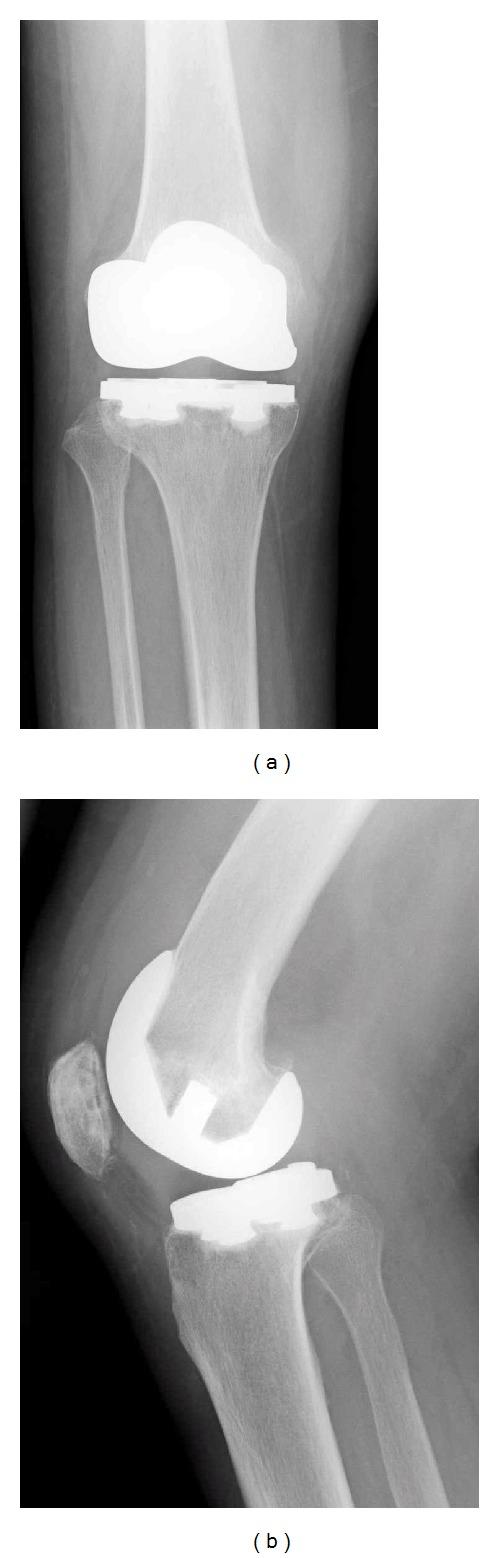

Arthroscopic debridement of the posterior compartment of the knee after total knee arthroplasty is difficult because it is tough to obtain intercondylar notch views. Herein, we performed arthroscopic debridement of the posterior compartment of an infected knee after total knee arthroplasty by using a transseptal portal in a 62-year-old woman with rheumatoid arthritis. Palpation of anatomical landmarks and posterior capsule protection are important for safe creation of a transseptal portal following to making 2 posterior portals.

全膝关节置换术后膝关节后间室的关节镜清理术操作困难,因为很难获得髁间窝视野。在此,我们对一名62岁类风湿关节炎女性患者采用经间隔入路,对全膝关节置换术后感染膝关节的后间室进行了关节镜清理术。在建立两个后外侧入路后,安全建立经间隔入路时,触诊解剖标志和保护后关节囊很重要。